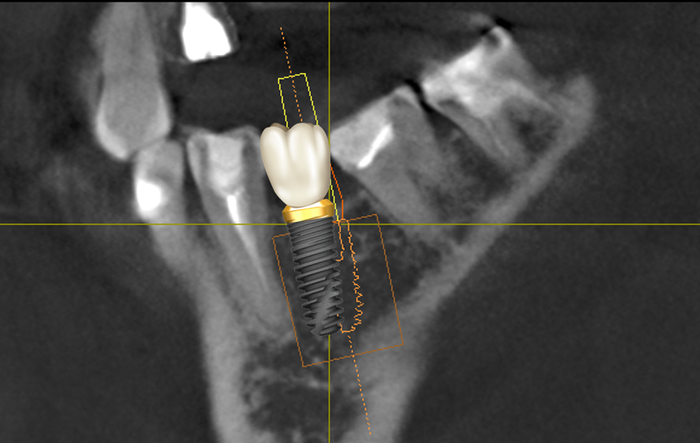

Имплантат в данной области должен располагаться примерно так:

В данном случае можно столкнуться с сложностями позиционирования имплантата, потому как наклон 7-го зуба препятствует правильному расположению сверла. Но это даже не самая большая проблема. Вся загвоздка в том, что в данном случае изготовить и установить коронку анатомический правильной формы будет невозможно. Ниже то, как (примерно) должен располагаться имплантат и коронка:

Прекрасно видно, что семерка мешает.